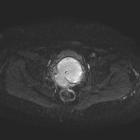

Rhabdomyosarkom des Uterus

Radiographic features

MRI

In the pelvis may add further to CT in delineated the tumor's relationship to adjacent organs and identifying lymph node disease.